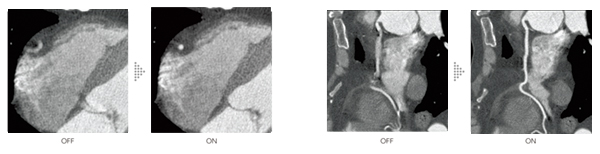

Cardio StillShot 心臓の動きによるモーションアーチファクトを抑える

Cardio StillShotは心臓CT検査で収集したRawDataから被写体の動く方向と量を4次元的に算出し,画像再構成時に補正を行うことで最高28msec*1の実効時間分解能を実現します。心拍の高い方でも動きによるブレの少ない高精細な臨床画像を提供します。